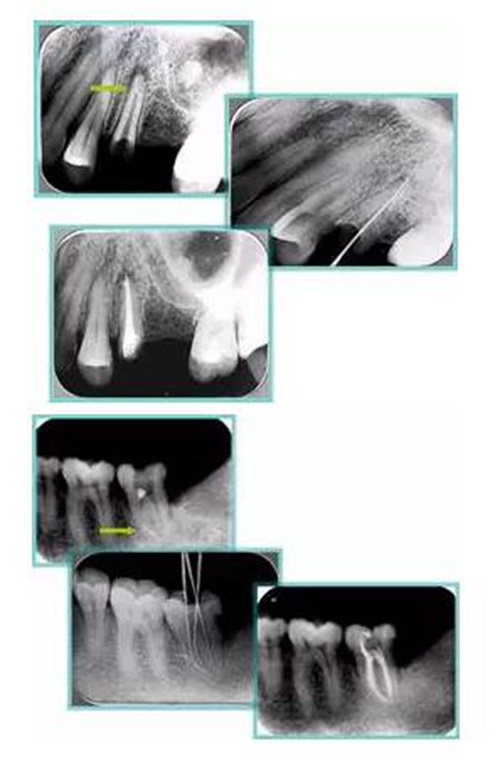

6. 鈣化

常見有修復(fù)性鈣化和增齡性鈣化。下面為根管鈣化 X 線片。

24.jpg

7. 器械折斷

下圖為器械折斷的 X 線片。箭頭處示折斷器械。

25.jpg

二、臺(tái)階

定義:根管內(nèi)壁上人為產(chǎn)生的不規(guī)則形狀阻止器械順利進(jìn)入根尖。

原因:器械沒有預(yù)彎,根向壓力過大。

下圖箭頭處示臺(tái)階形成。

26.jpg

2. 側(cè)穿

( 1 )定義:根管側(cè)壁過度切削過薄以至穿孔。( 2 )原因:根中區(qū)域的過度切削,特別是上頜磨牙的近中頰根和下頜磨牙的近中根 。

27.jpg